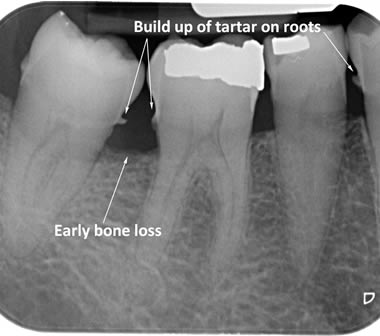

The diagrams below show the different stages of gum disease

Calculus (tartar) is the hard deposit which forms on the teeth in areas where plaque is left undisturbed. Calculus is too hard to brush off with a toothbrush and needs to be removed by the Dental Hygienist with special scaling instruments.